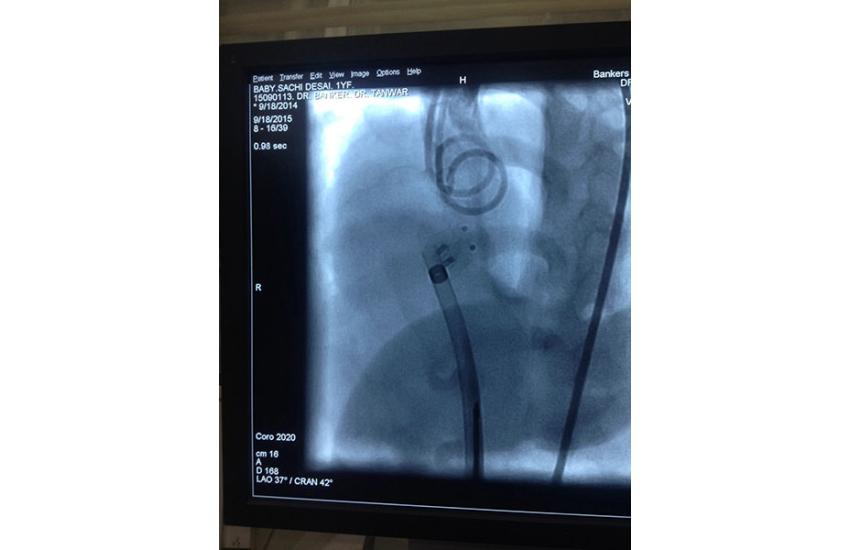

CAG revealed normal coronaries,holter shows sinus bradycardia,RBBB with LAHB,intermittent AF, TMT shows blunted chronotropic response and hypotensive response so he has been planned for PPI with back up of pacemaker patient treated with beta blockers and corderone,after 7 days of PPI,he has undergone alcohol septal ablation successfully,prior his dynaemic gradient was 50 mmhg in rest n 80 mmhg with exercise which reduced to 20mmhg after procedure. Now patient is under close follow up so will continue updating.